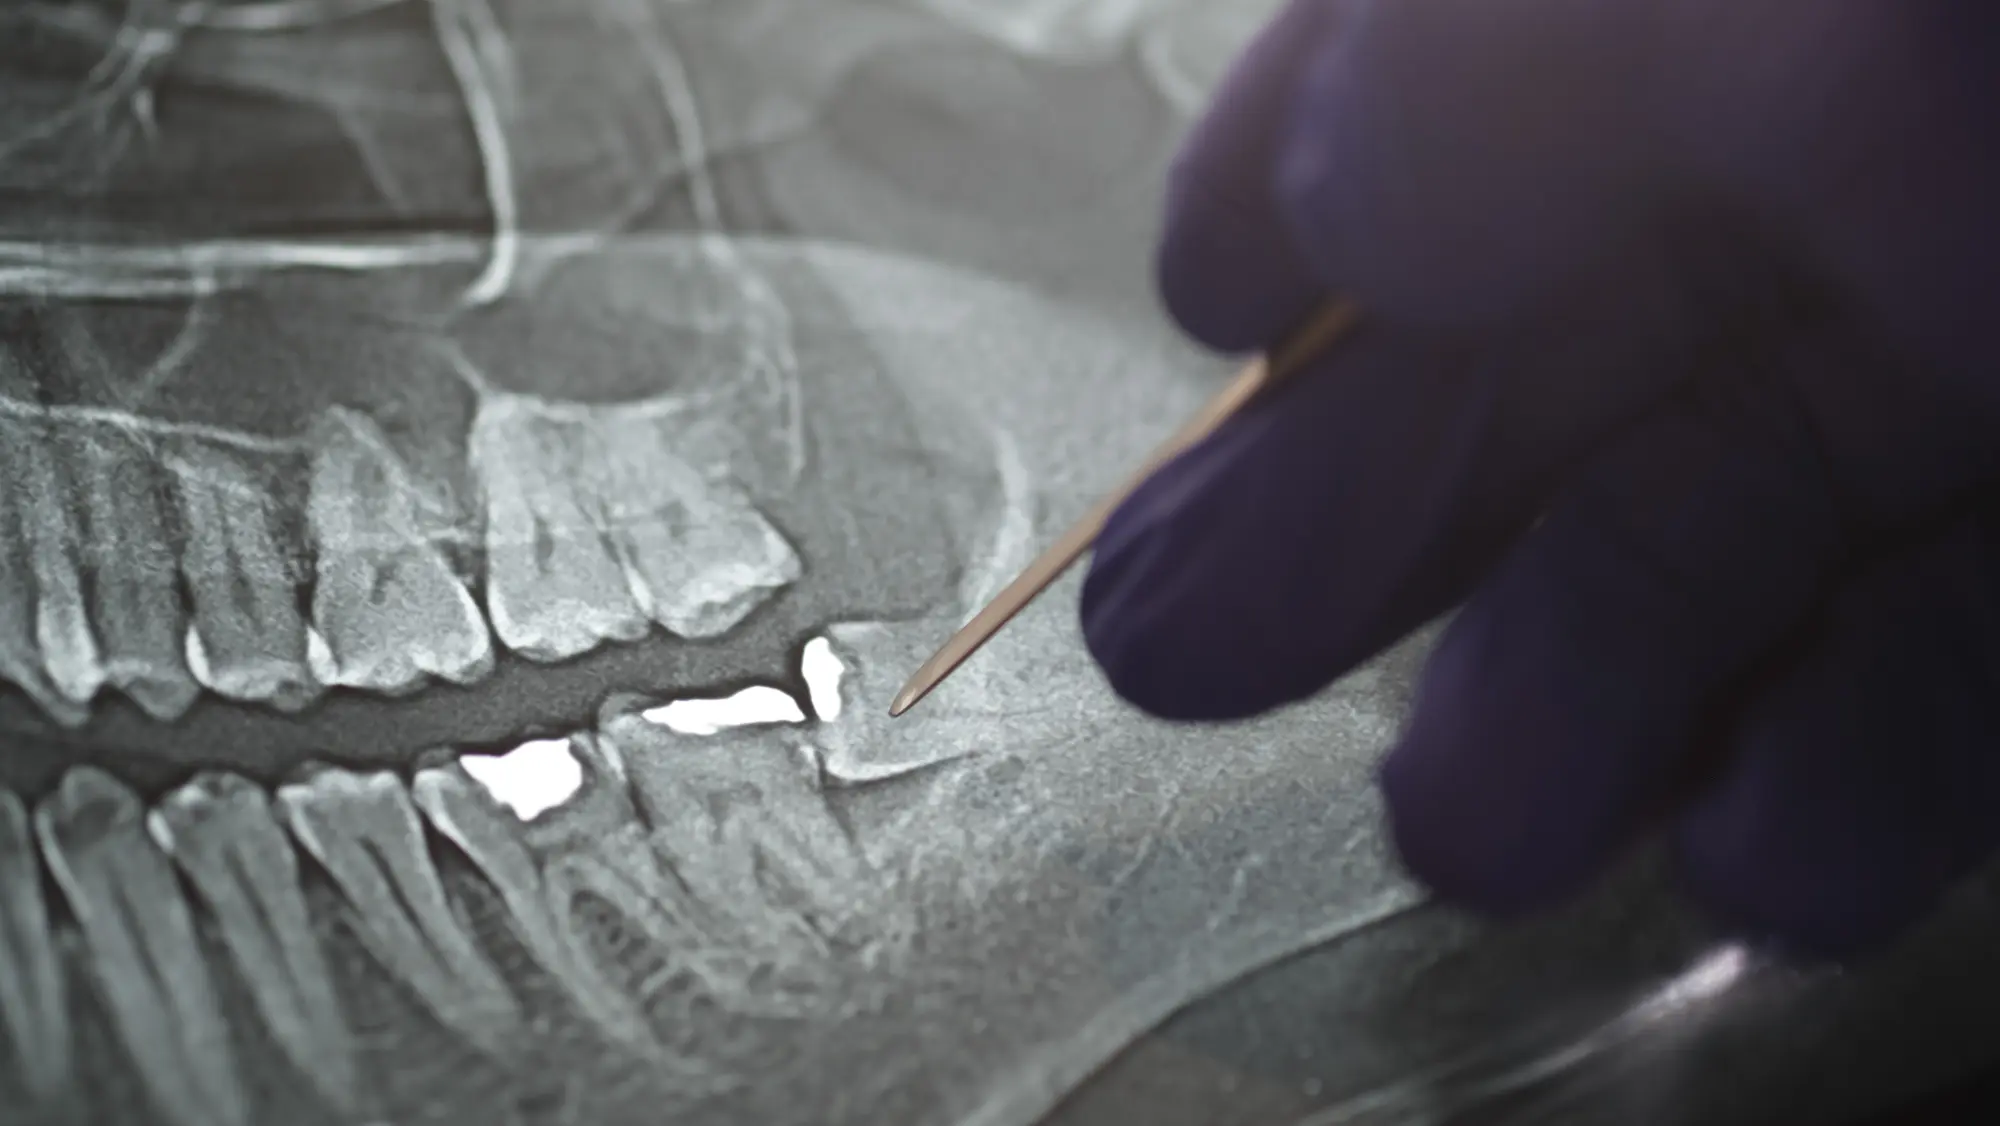

Belterra X-Rays: What Your Dentist Sees in Your Oral Health Screening

If you’ve ever wondered what your dentist is really looking at when viewing your dental X-rays, you’re not alone. At Renken Dentistry Belterra in Austin, we know that being informed about your care helps ease nerves and builds trust. That’s why we take the time to show patients what we’re seeing during their oral health […]